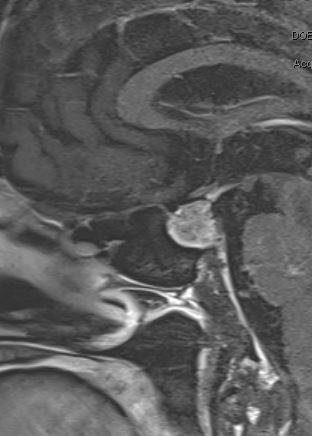

Amy’s husband, Jeff, is a house painter and was working at a local physician’s house. Upset and confused that his wife was continuing to suffer, Jeff struck up a conversation with the doctor to pass the time, in the hopes of any helpful insight into his wife’s condition. This doctor listened, recognized some of the red flags, suggested a number of new possible diagnoses and offered to see Amy in clinic. Surprised by this doctor’s attention to detail, empathy and willingness to listen, Jeff suggested that Amy seek a second opinion. Amy felt like she had nothing to lose so went to see the PCP in short order. After a battery of tests, including an MRI of the brain, Amy was diagnosed with a pituitary tumor. As scary as the diagnosis was, Amy was relieved and thankful that she had an answer about the source of her suffering. Amy’s doctor referred her to the pituitary program at the University of Rochester (UR), and as Amy was preparing for her upcoming visit, another random interaction added a further personal dimension to her case.

Jeff was working on another painting project when small talk led to the revelation that he was working at the house of Ed Vates, MD, PhD, FAANS, a skull base neurosurgeon, the surgical director of the UR Medicine Pituitary Program and the neurosurgeon Amy was scheduled to see. At her office visit, Dr. Vates explained that she had a prolactinoma. He explained to her the reason for her galactorrhea and amenorrhea. They spent the remainder of the visit discussing the various options, and after extensive discussion with Dr. Vates and the endocrinologist, Amy agreed with the recommendation of medical management. Unfortunately, Amy experienced significant side effects from both cabergoline and bromocriptine, and after another consultation with Dr. Vates, she decided to proceed with endoscopic pituitary surgery.